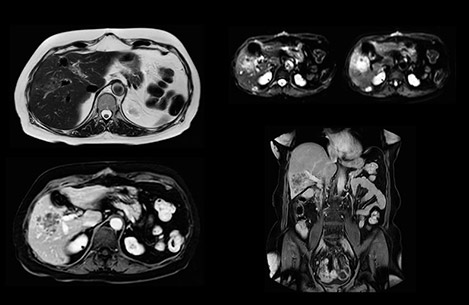

“Our liver exams are quite fast,” says Dr. Baumann. “If the patient tolerates it, we use an arms-up position to reduce the FOV and speed up the exam with dS SENSE.” “We acquire one transversal high resolution T2-weighted sequence with 3 mm slice thickness, for example for pancreas or liver lesions. Then we also add a T2 fat suppressed MultiVane XD SPIR sequence. We perform these two routinely in our liver imaging. We use high dS SENSE factors to significantly shorten scan times to 2-4 minutes, which can improve our protocol; it’s a very robust scan.” “We include mDIXON for the dynamic sequences because of the robust and homogeneous fat suppression we get with that. We had been using eTHRIVE, but we are now quite happy with mDIXON. Sometimes we use a medication to calm the bowels, to further improve the image quality.”

Dr. Baumann then implemented MultiVane XD for motion correction. It uses an extended reconstruction algorithm for imaging that is virtually motion free. “With MultiVane XD we get excellent motion-corrected images with high spatial resolution. We typically first optimize our scan for high image quality, and when satisfied with that, we try to reduce the scan time. So, we combined MultiVane XD with dS SENSE, which allows us to shorten the scan time,” he explains. “The performance of MultiVane XD in liver imaging is outstanding. MultiVane XD with dS SENSE is a powerful development in improving liver image quality.” “As we use breathhold imaging for T2-weighted liver scans, we depend on the patient’s ability to cooperate with the exam. This can present a real challenge when we are looking for small lesions, such as in our oncological patients. However, with MultiVane XD motion correction, we get excellent images. This is important for our surgeons, because they want to know exactly where the lesions are.”

“We are more confident in our diagnosis if we don’t have to rescan the patient and compare it to other studies; this liver exam gives us good image quality in a faster time than the default system’s approach with arms down. That makes a difference for the patients, too. The shorter scan times, especially with the high dS SENSE factors, shorten the duration of the total examination. At the same time it’s more comfortable for the patient, to rest normally without holding the breath, just relaxing.”